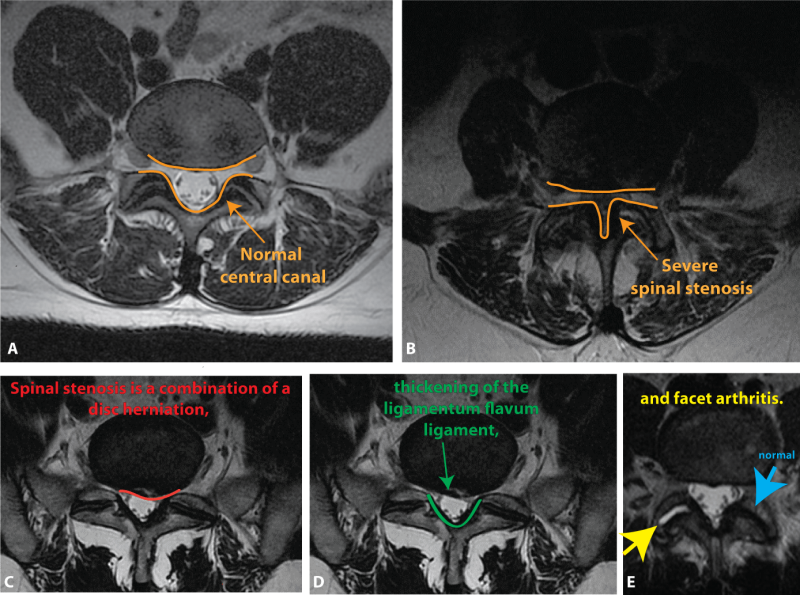

상기의 내용을 보고 계시지 않는 때문에 쉽게 설명 하자면 협착증은 척추 구조물인 허리통(foraminal)에 따라서 뇌에서 연결된 척수(spimal cord)이 지나는 공간을 말합니다. 이런 척수가 지나가기 때문의 공간에는 양쪽의 후궁(lamina)촉각을 덮고 황색 인대(flavum ligament)이 존재하지만 다양한 이유로 척수가 지나는 공간이 좁아지는 통증을 호소하는 현상을 말합니다! 그럼 오늘 본 내용에 와서 척추 협착증 때 나타나는 복사 통과 수술에 대해서 봅시다!먼저 척추별 복사 모습의 위치입니다!!척추 협착증이 있을 때, 경추 또는 요추로 그 증상이 나타났을 때 그 부위에서 통증이 아니라 손발에 방사 통(radiatin)가 나타납니다!방사 통의 위치에 의해서 손상된 척추의 위치가 의심되는 것이 있는데, 아래의 그림을 통해서 척추별 복사 모습의 위치를 한번 알아보겠습니다!!

척추 구조물을 보면 양쪽으로 뻗기 위한 횡돌기(transverse process)가 존재하고 있습니다.여기서 중간으로 이어지는 후궁(lamina)이 존재합니다.디스크 구멍이 좁아지는 이유 중 가장 큰 원인은 황색인대가 비대해지기 때문입니다!황색인대는 위에서 설명한 것처럼 신경과 신경을 덮는 기능을 하고 있습니다! 후궁 앞에 황색인대가 비대해지면 추간판공의 공간이 좁아지고 이를 통과하는 척수에 압력이 가해져요!